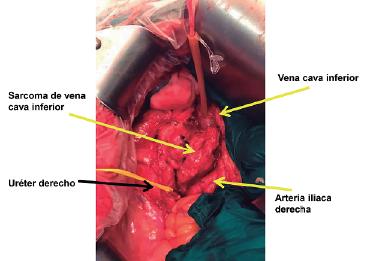

Imágenes y Cirugía

Natalia González Alcolea, María Dolores Chaparro Cabezas, Félix Martínez Arrieta, Victor Sánchez Turrión